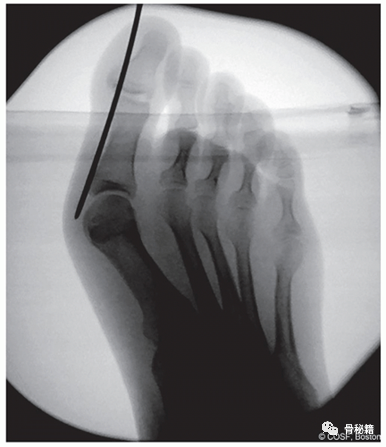

透视图像显示了计划的截骨位置。

计划的切口位置。钢丝不应穿透骨骼,应保持在骨膜外平面。

针在拇趾软组织骨外位置的透视图像。